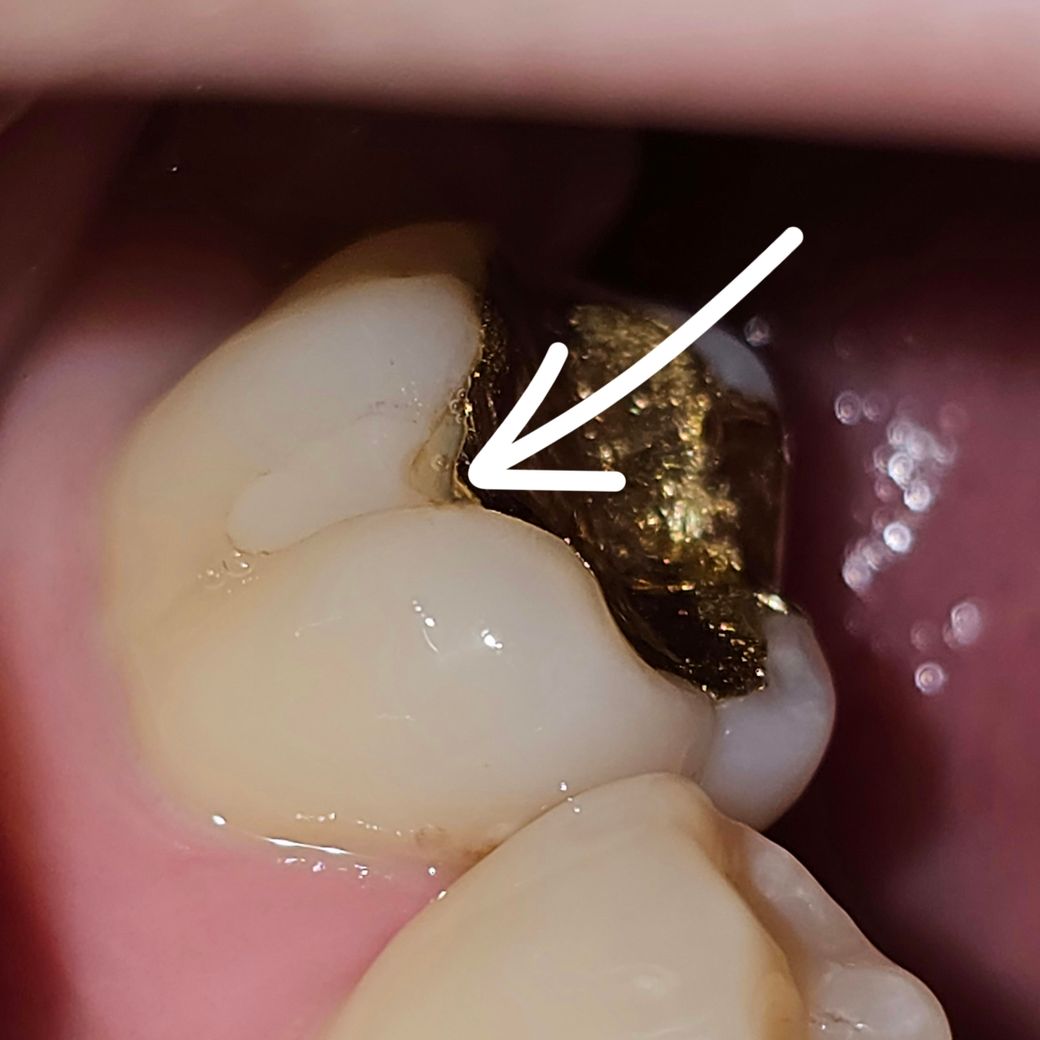

충치일까요? 확인 해 주시면 감사하겠습니다.

다니는 치과에 일년 전 부터 금인레이에 파절이 있는 것 같다고 이야기 했는데

치과에서는 구멍난 부위는 안보인다고 빛이 반사된 걸 잘 못 본거라고 했거든요..

오늘 거울로 확인 해 보니 좀 많이 수상 해 보이는 곳이 보여서 올려봅니다..

사진은 전부 한 치아 입니다.

1. 인레이 밑으로 충치가 생긴 걸까요? 아니라면 뭘까요?

• 1번 째 사진

인레이 하방으로 치아가 조금 깨진부분도 잇고 틈새가 생긴거 같습니다. 저정도면 관리하면서 사용하셔도 크게 문제가 되진 않을것같습니다.

사진으로 봤을 경우에는 인레이 보철물이 조금 떠있는것처럼 보이기는 합니다. 내부의 충치 여부는 육안으로보다 방사선 사진이 있어야 더 정확하게 판단할수 있을것으로 생각됩니다.